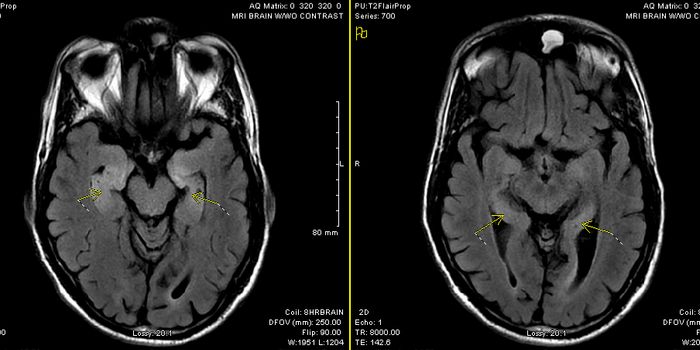

MAY 04, 2016NeuroscienceRupture of small blood vessels in the brain can cause hemorrhagic stroke and brain microbleeds, and finding the fastest ...

JAN 28, 2016NeuroscienceWhen a patient suffers a stroke, the key factor is time. Neurologists call it a Golden Window where “time is brain ...

NOV 19, 2015Clinical & Molecular DXCould a shorter brain fold be diagnostic of hallucinations associated with schizophrenia? After analyzing the MRI scans ...